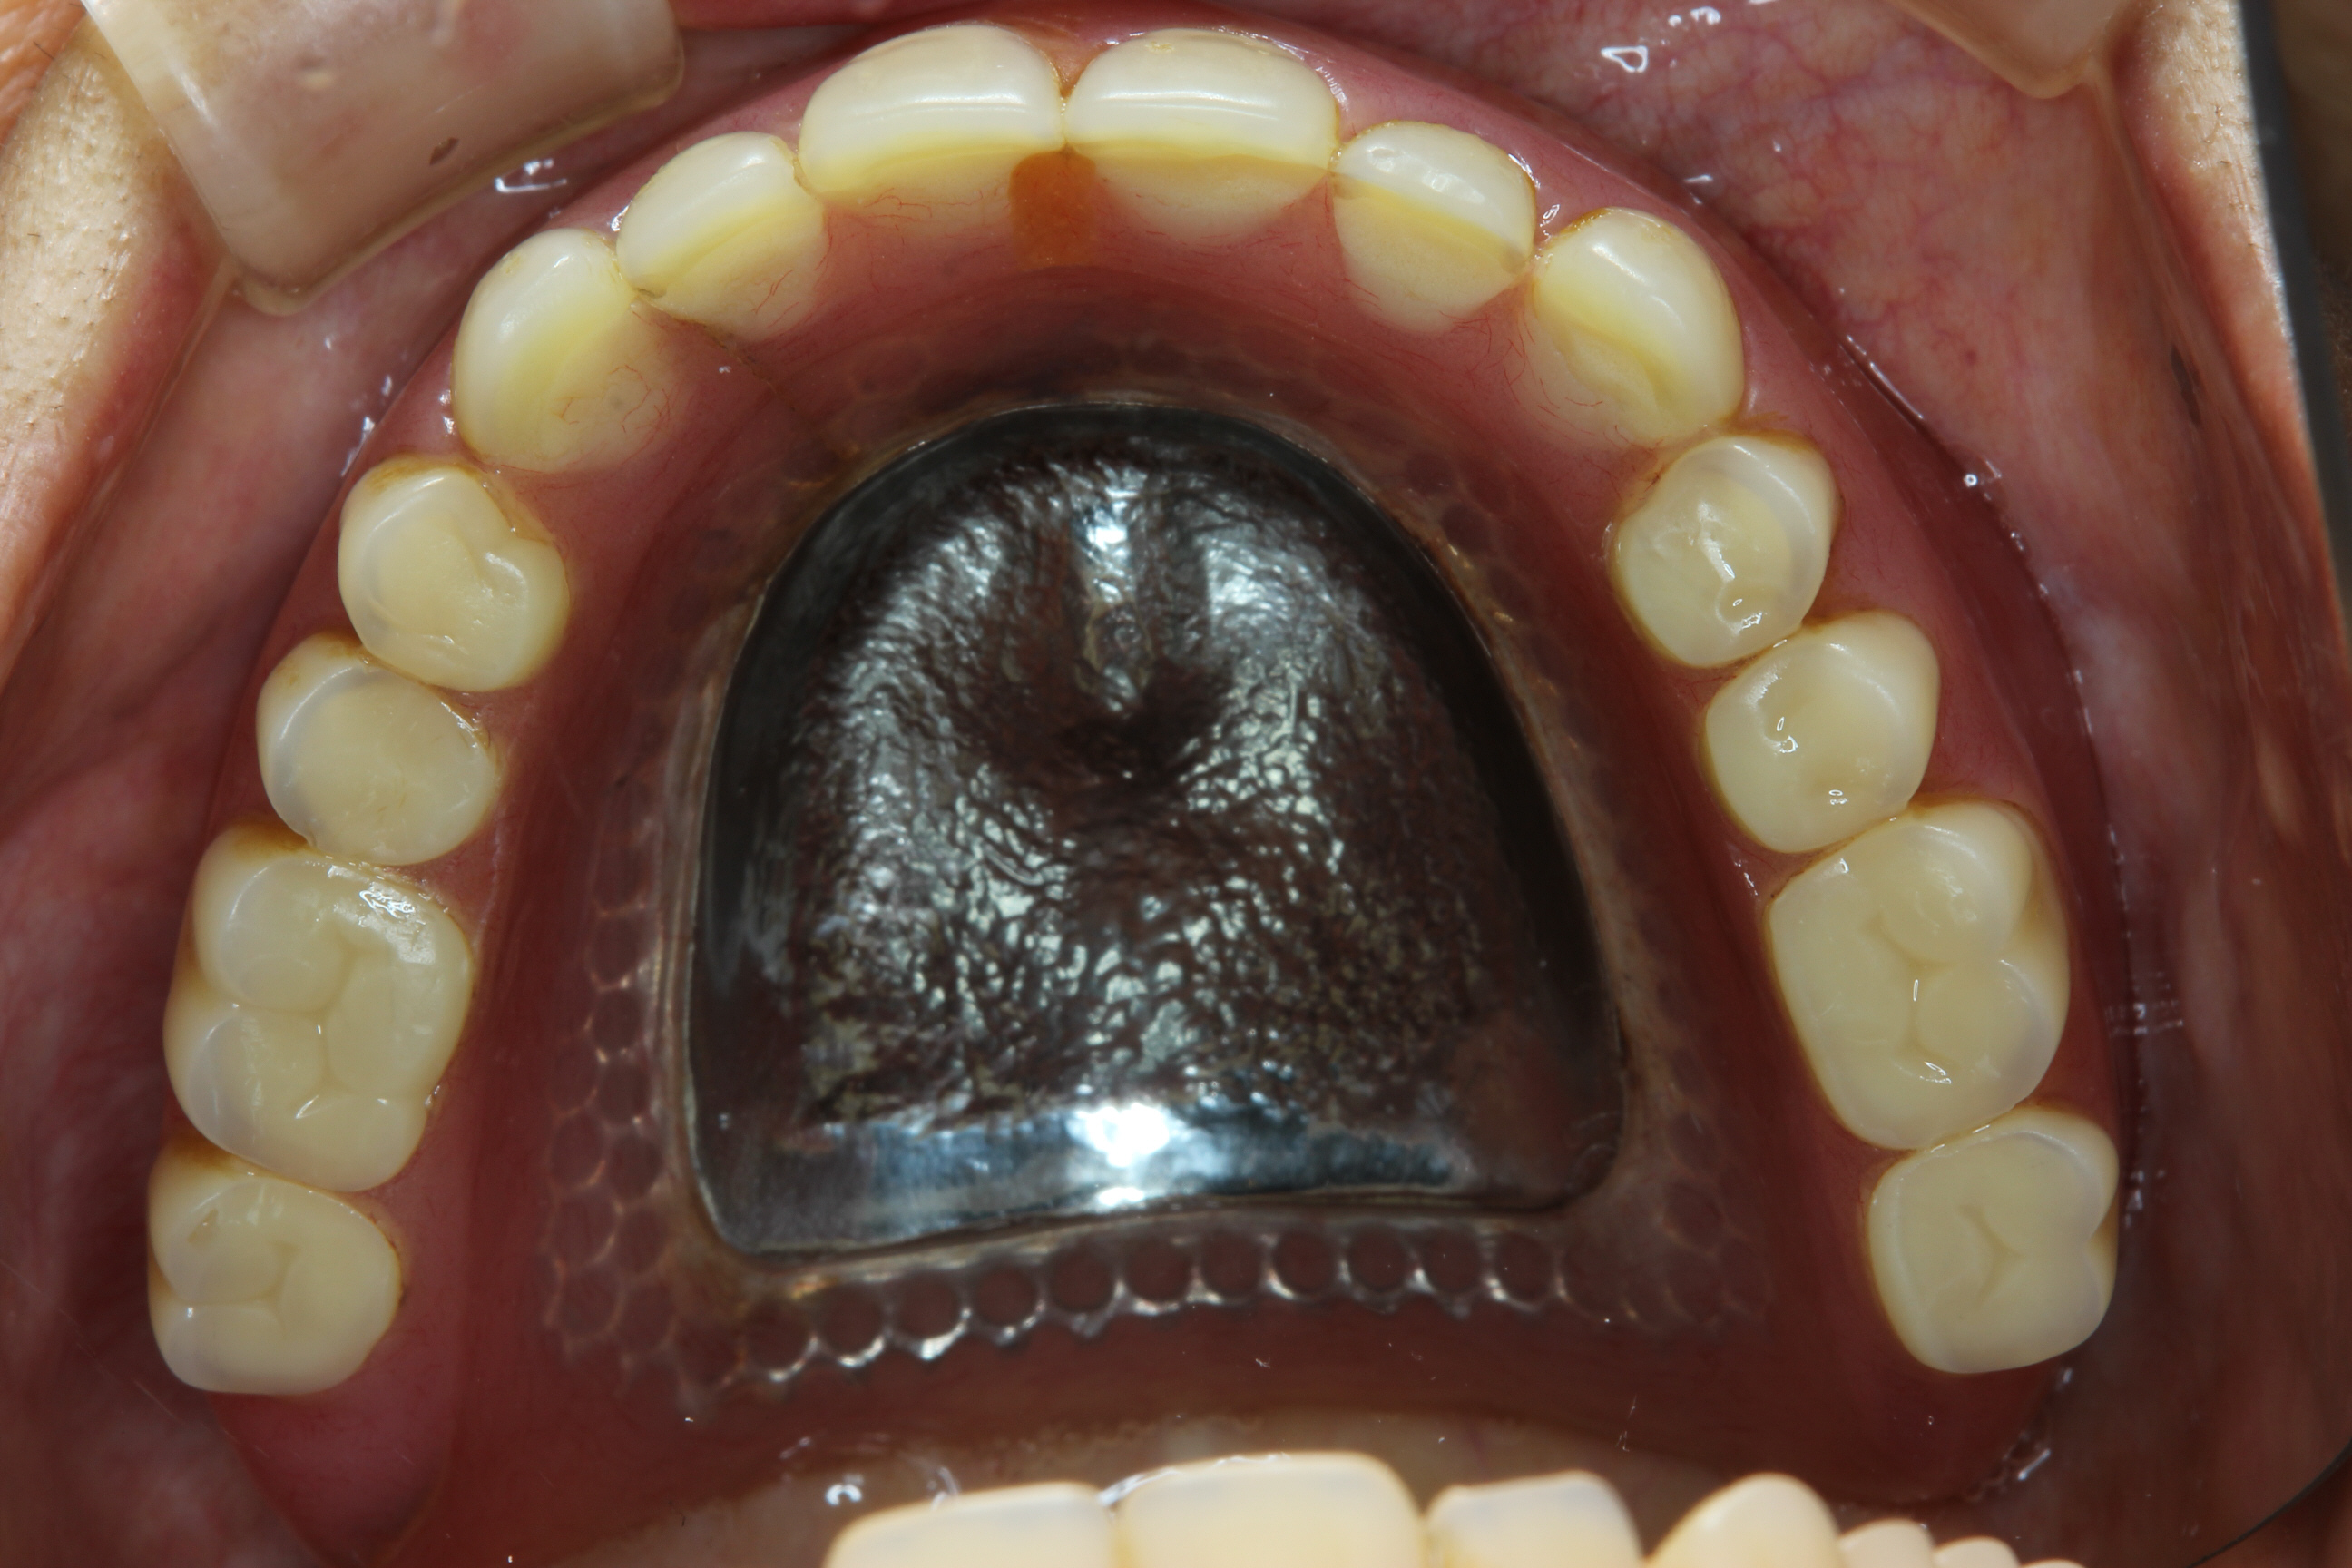

下の写真は治療後です。

上下の義歯は、チタンを用いた金属床義歯、下顎の残存歯は、すべてメタルセラミックスクラウンです。

義歯の重要な部分にチタンなどの金属を用いることで、破折を防ぐだけでなく、とても薄い義歯にすることができ、違和感の少ない義歯ができます。